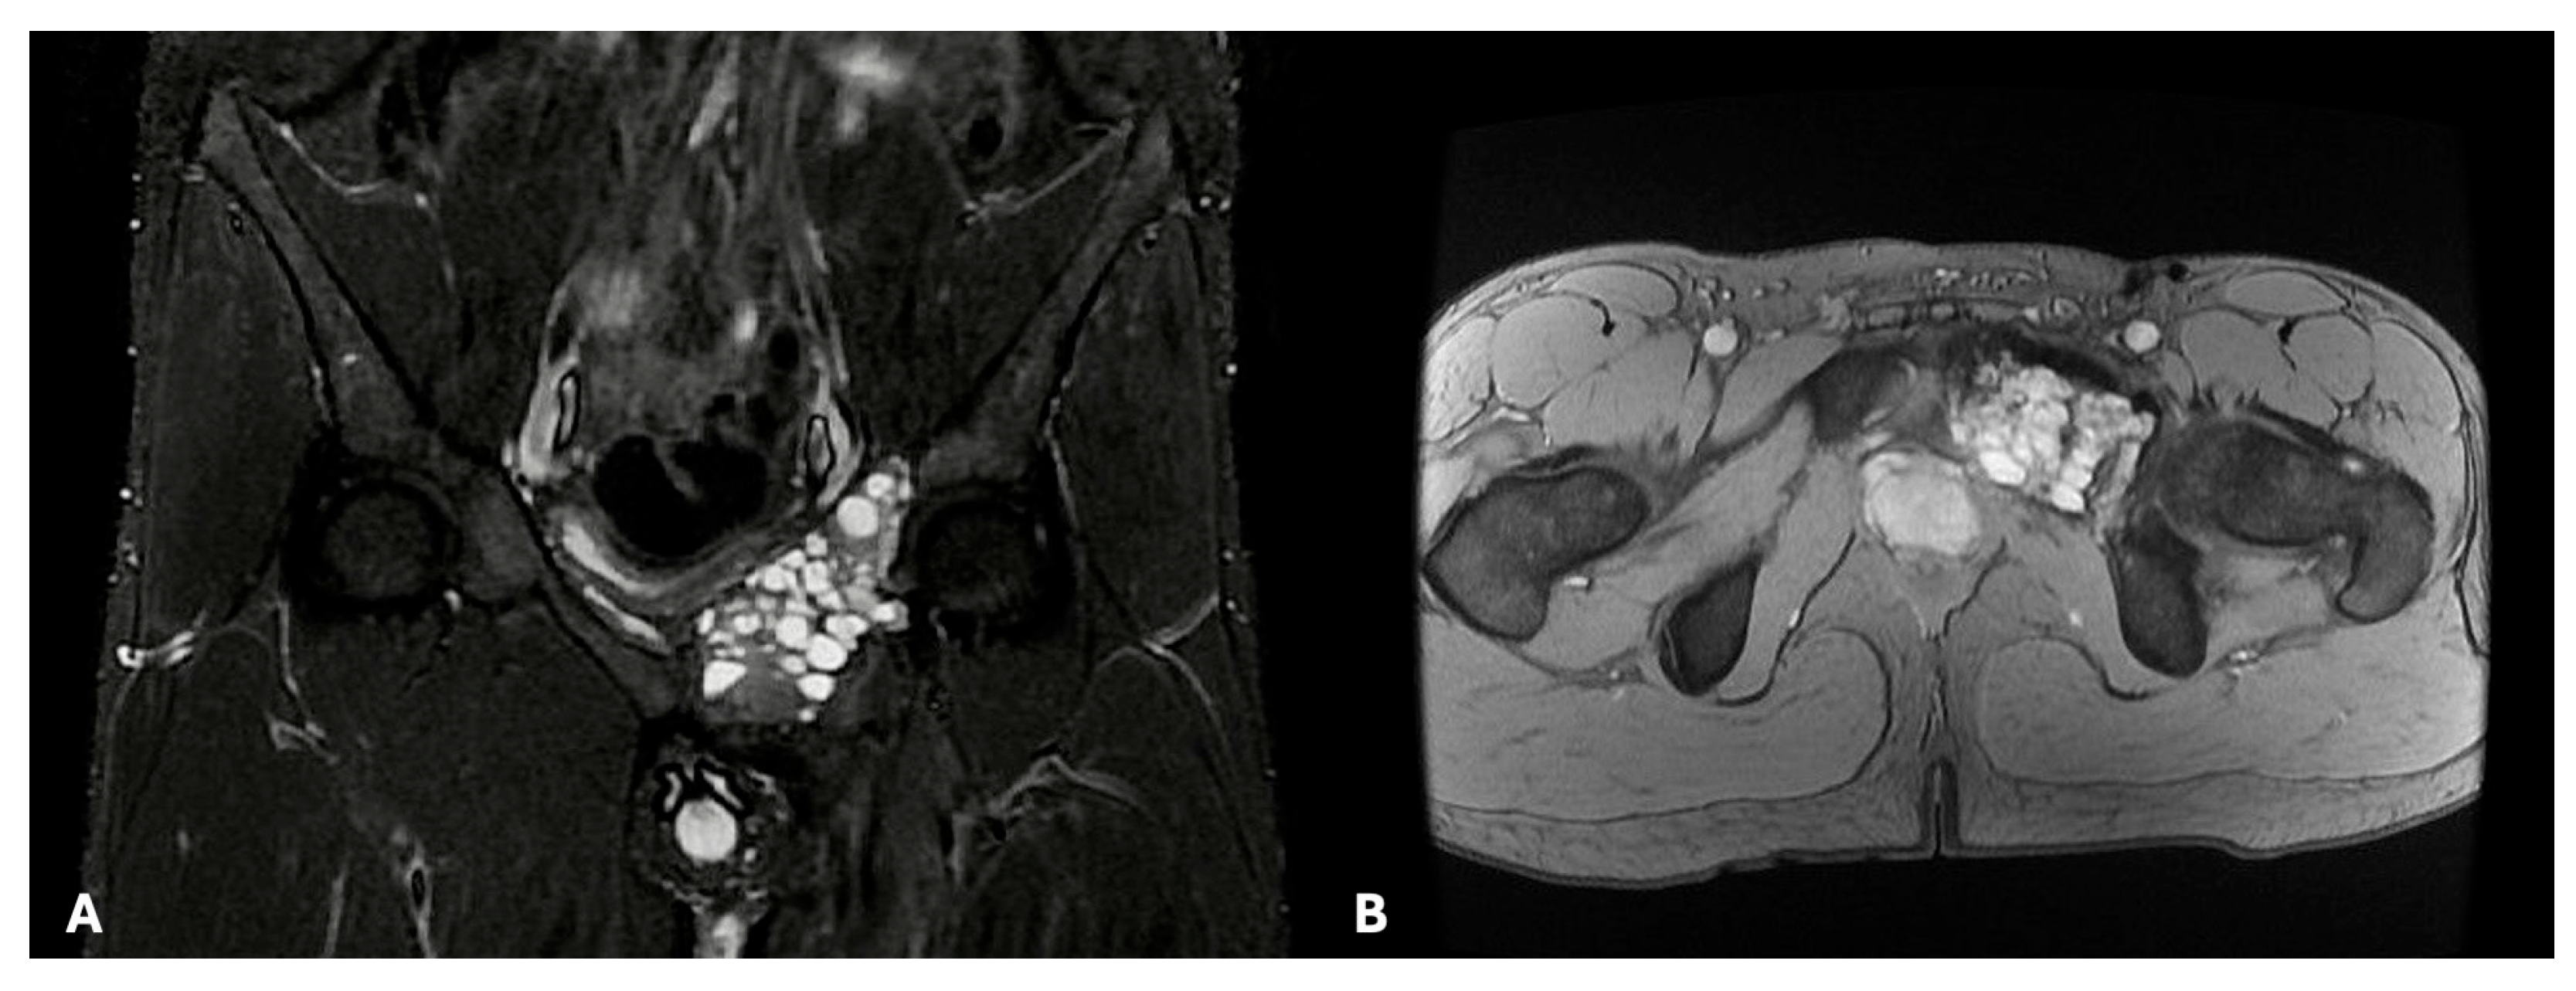

- Stefanidis, K.; Benakis, S.; Tsatalou, E.; Ouranos, V.; Chondros, D. Computed tomography and magnetic resonance imaging of desmoplastic fibroma with simultaneous manifestation in two unusual locations: A case report. J. Med. Case Rep. 2011, 5, 28. [Google Scholar] [CrossRef]